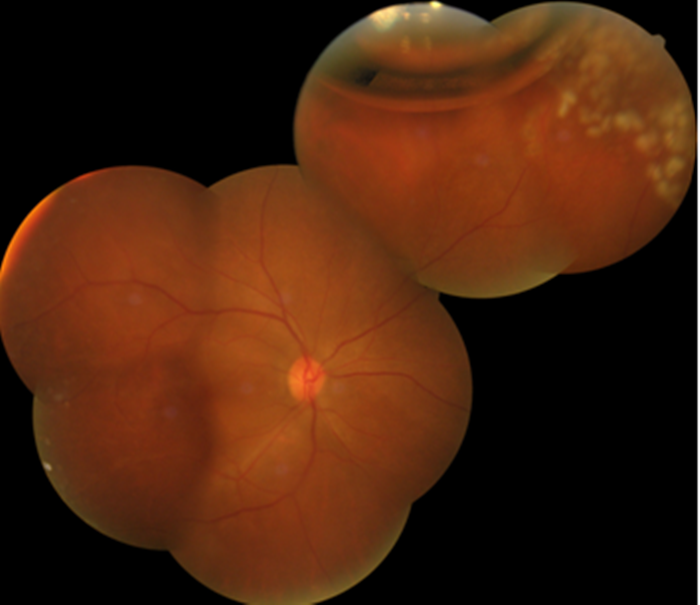

眼底檢查術(shù)前

眼底檢查術(shù)后